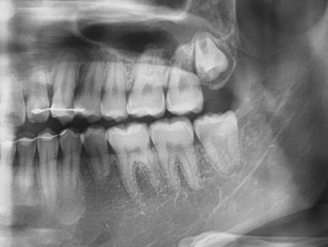

또는 사랑니가 나오지 않아서 없는줄 알았다가 우연히 치과에서 파노라마를 찍고 나서 잇몸 안에 매복되어 있는 사랑니를 발견하고 울상이 되어버리는 분들도 계십니다.

▶ 특징: 치아 머리가 잇몸 밖으로 일부 보이지만, 치아가 기울어져 있는 상태입니다. 엑스레이로 확인했을 때 치아가 옆으로 눕거나 사선으로 경사져 있는 경우가 많습니다.

▶ 특징: 치아 전체가 잇몸 속에 깊숙이 매복된 상태로, 육안으로는 전혀 보이지 않습니다. 치아 뿌리가 신경과 가까운 경우가 많아 발치 시 주의가 필요합니다.